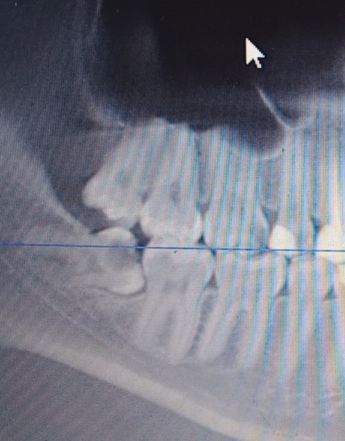

В стоматологии сделали снимок, на снимке видно и пульпит в молочных, у которых заметно рассасываются корни, и видны уже хорошо сформированные коренные в десне.